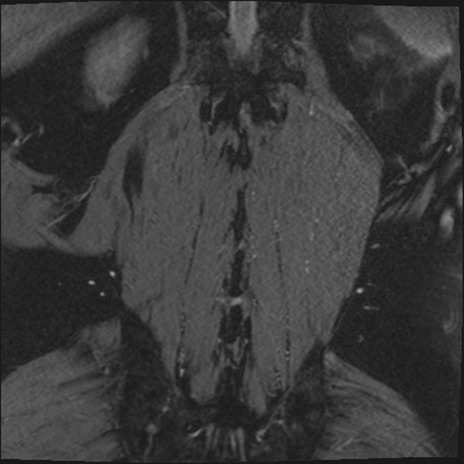

【整形】TIPS症例2 腰椎MRI 3D(冠状断像)

【症例】70歳代男性

【主訴】左下肢痛

【現病歴】2週間前くらいから腰痛、左下肢痛あり。左臀部から大腿、下腿外側のしびれが常時ある。歩行とともに同部位の痛みあり。

【身体所見】Lasegue70-/60+、Bragard-/±、PTR ±/±、ATR -/-、IP 5/5、TA 5/4、TS 5/5、EHL 右第1足趾なし/3、FHL 5/5、hypersthesia(-)、足背動脈触知良好

異常所見と診断は?